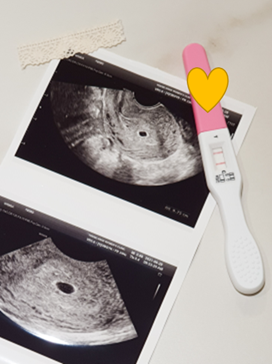

배란일 10일차 (생리예정일 4일 전)

얼리임테기를 사용해서 테스트를 해봤다.

희미하게 두줄을 확인할 수 있었다.

배란일 19일차 (생리예정일 5일 후)

애기집 못볼수 있다고 하셨찌만 쌤께서 애기집 찾아서 보여주셨다.

남편도 초음파실로 들어오라고 부르셨다.

남편이 들어오자 마자 큰소리로 우아~ 했다;;